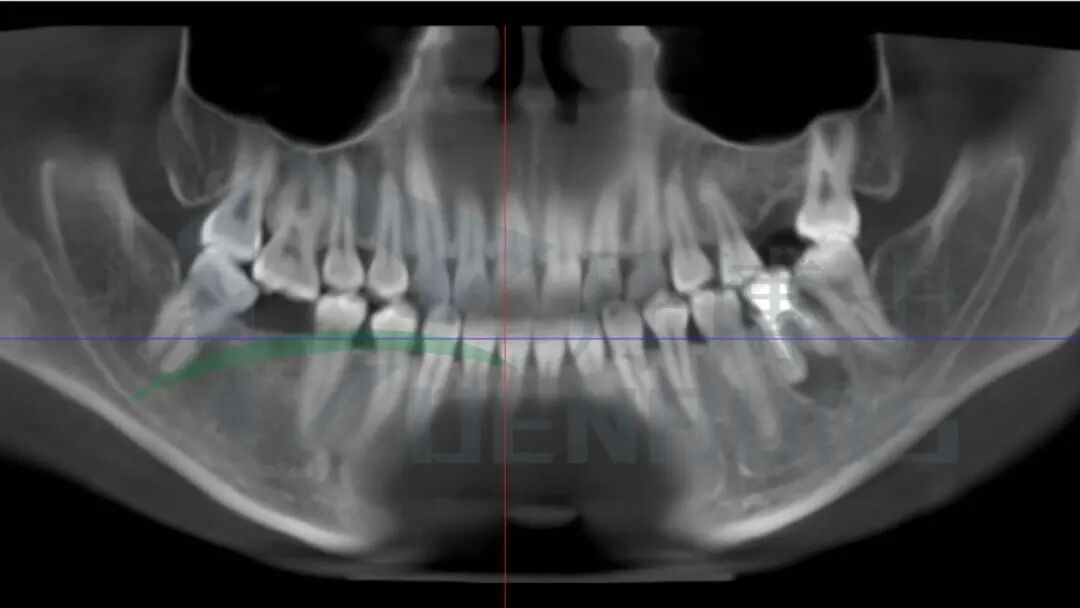

影像学检查与诊断

全景片显示:

26、46缺失;36根管内高密度,根尖椭圆形透射影

诊断:

• 36根尖囊肿

• 根管治疗后

阻力分析

• 根管治疗后的牙体变脆

• 近远中牙根膨大: 牙根阻力

• 种植需要尽可能微创,保留剩余非炎症区域牙槽骨